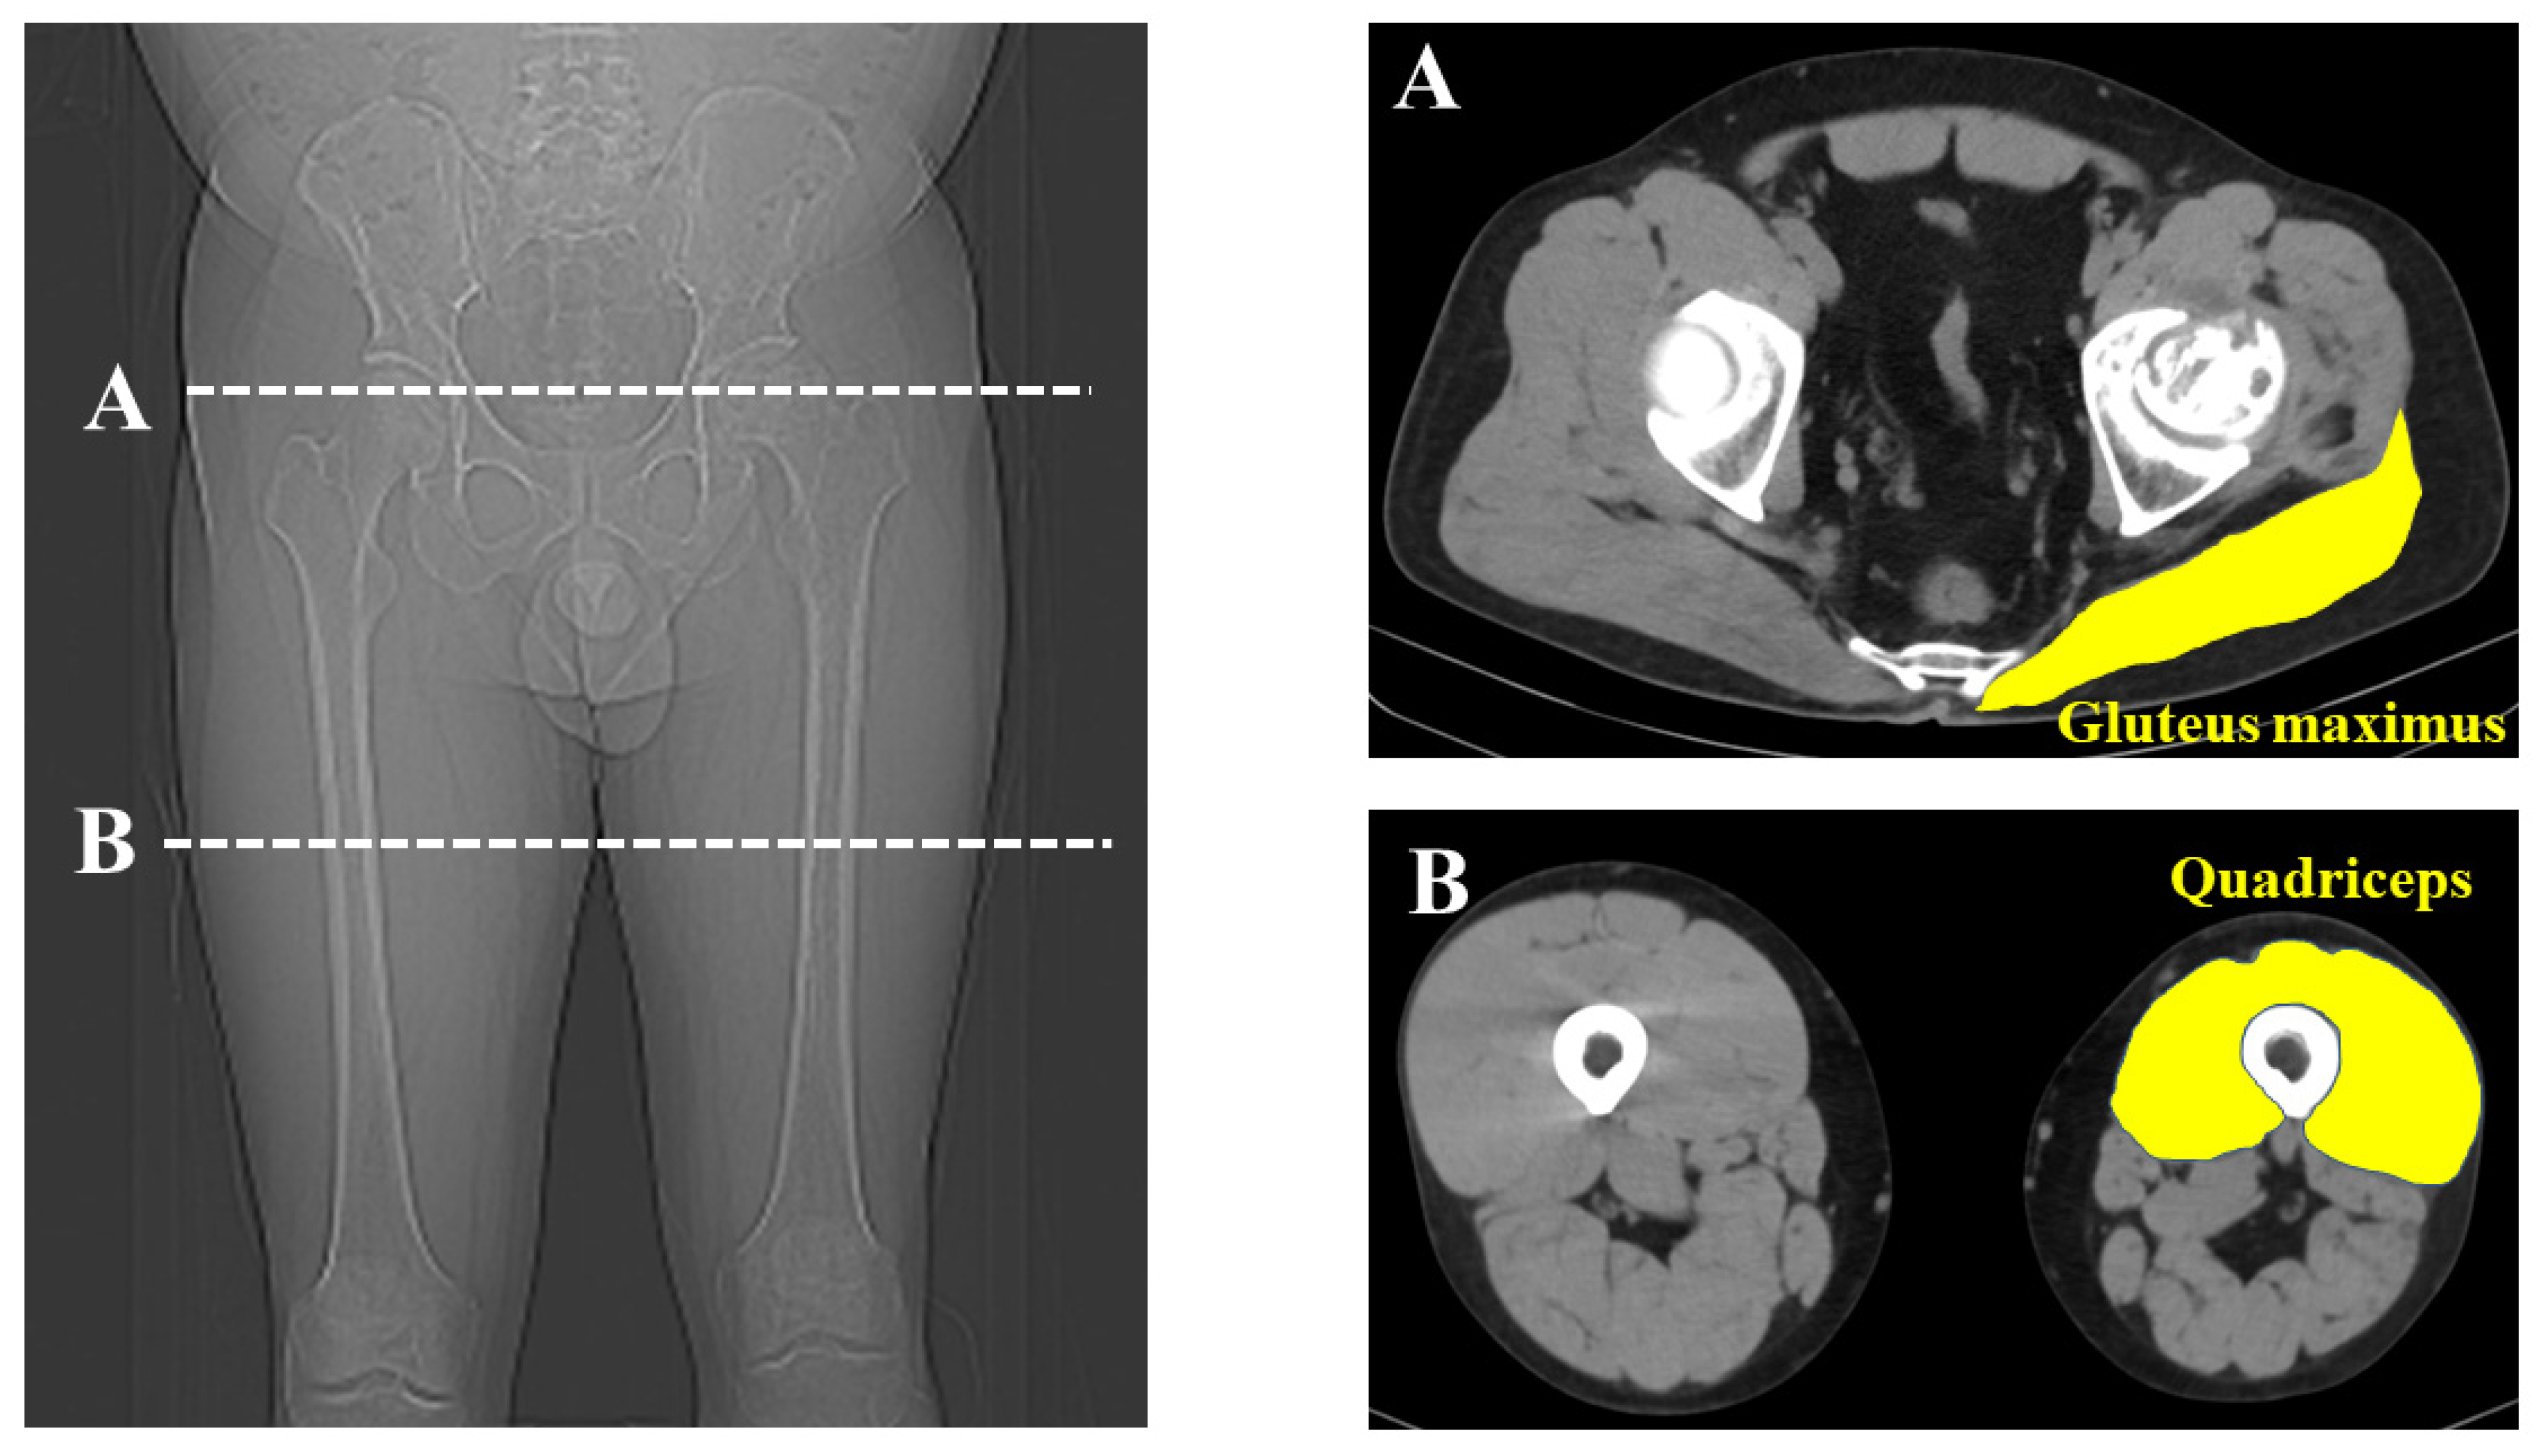

| Muscle volume of gluteus maximus (mm2/kg) | 45.9 ± 10.4 | 51.1 ± 9.2 | <0.01 * |

| Muscle volume of quadriceps (mm2/kg) | 65.5 ± 13.1 | 70.6 ± 13.1 | <0.01 * |